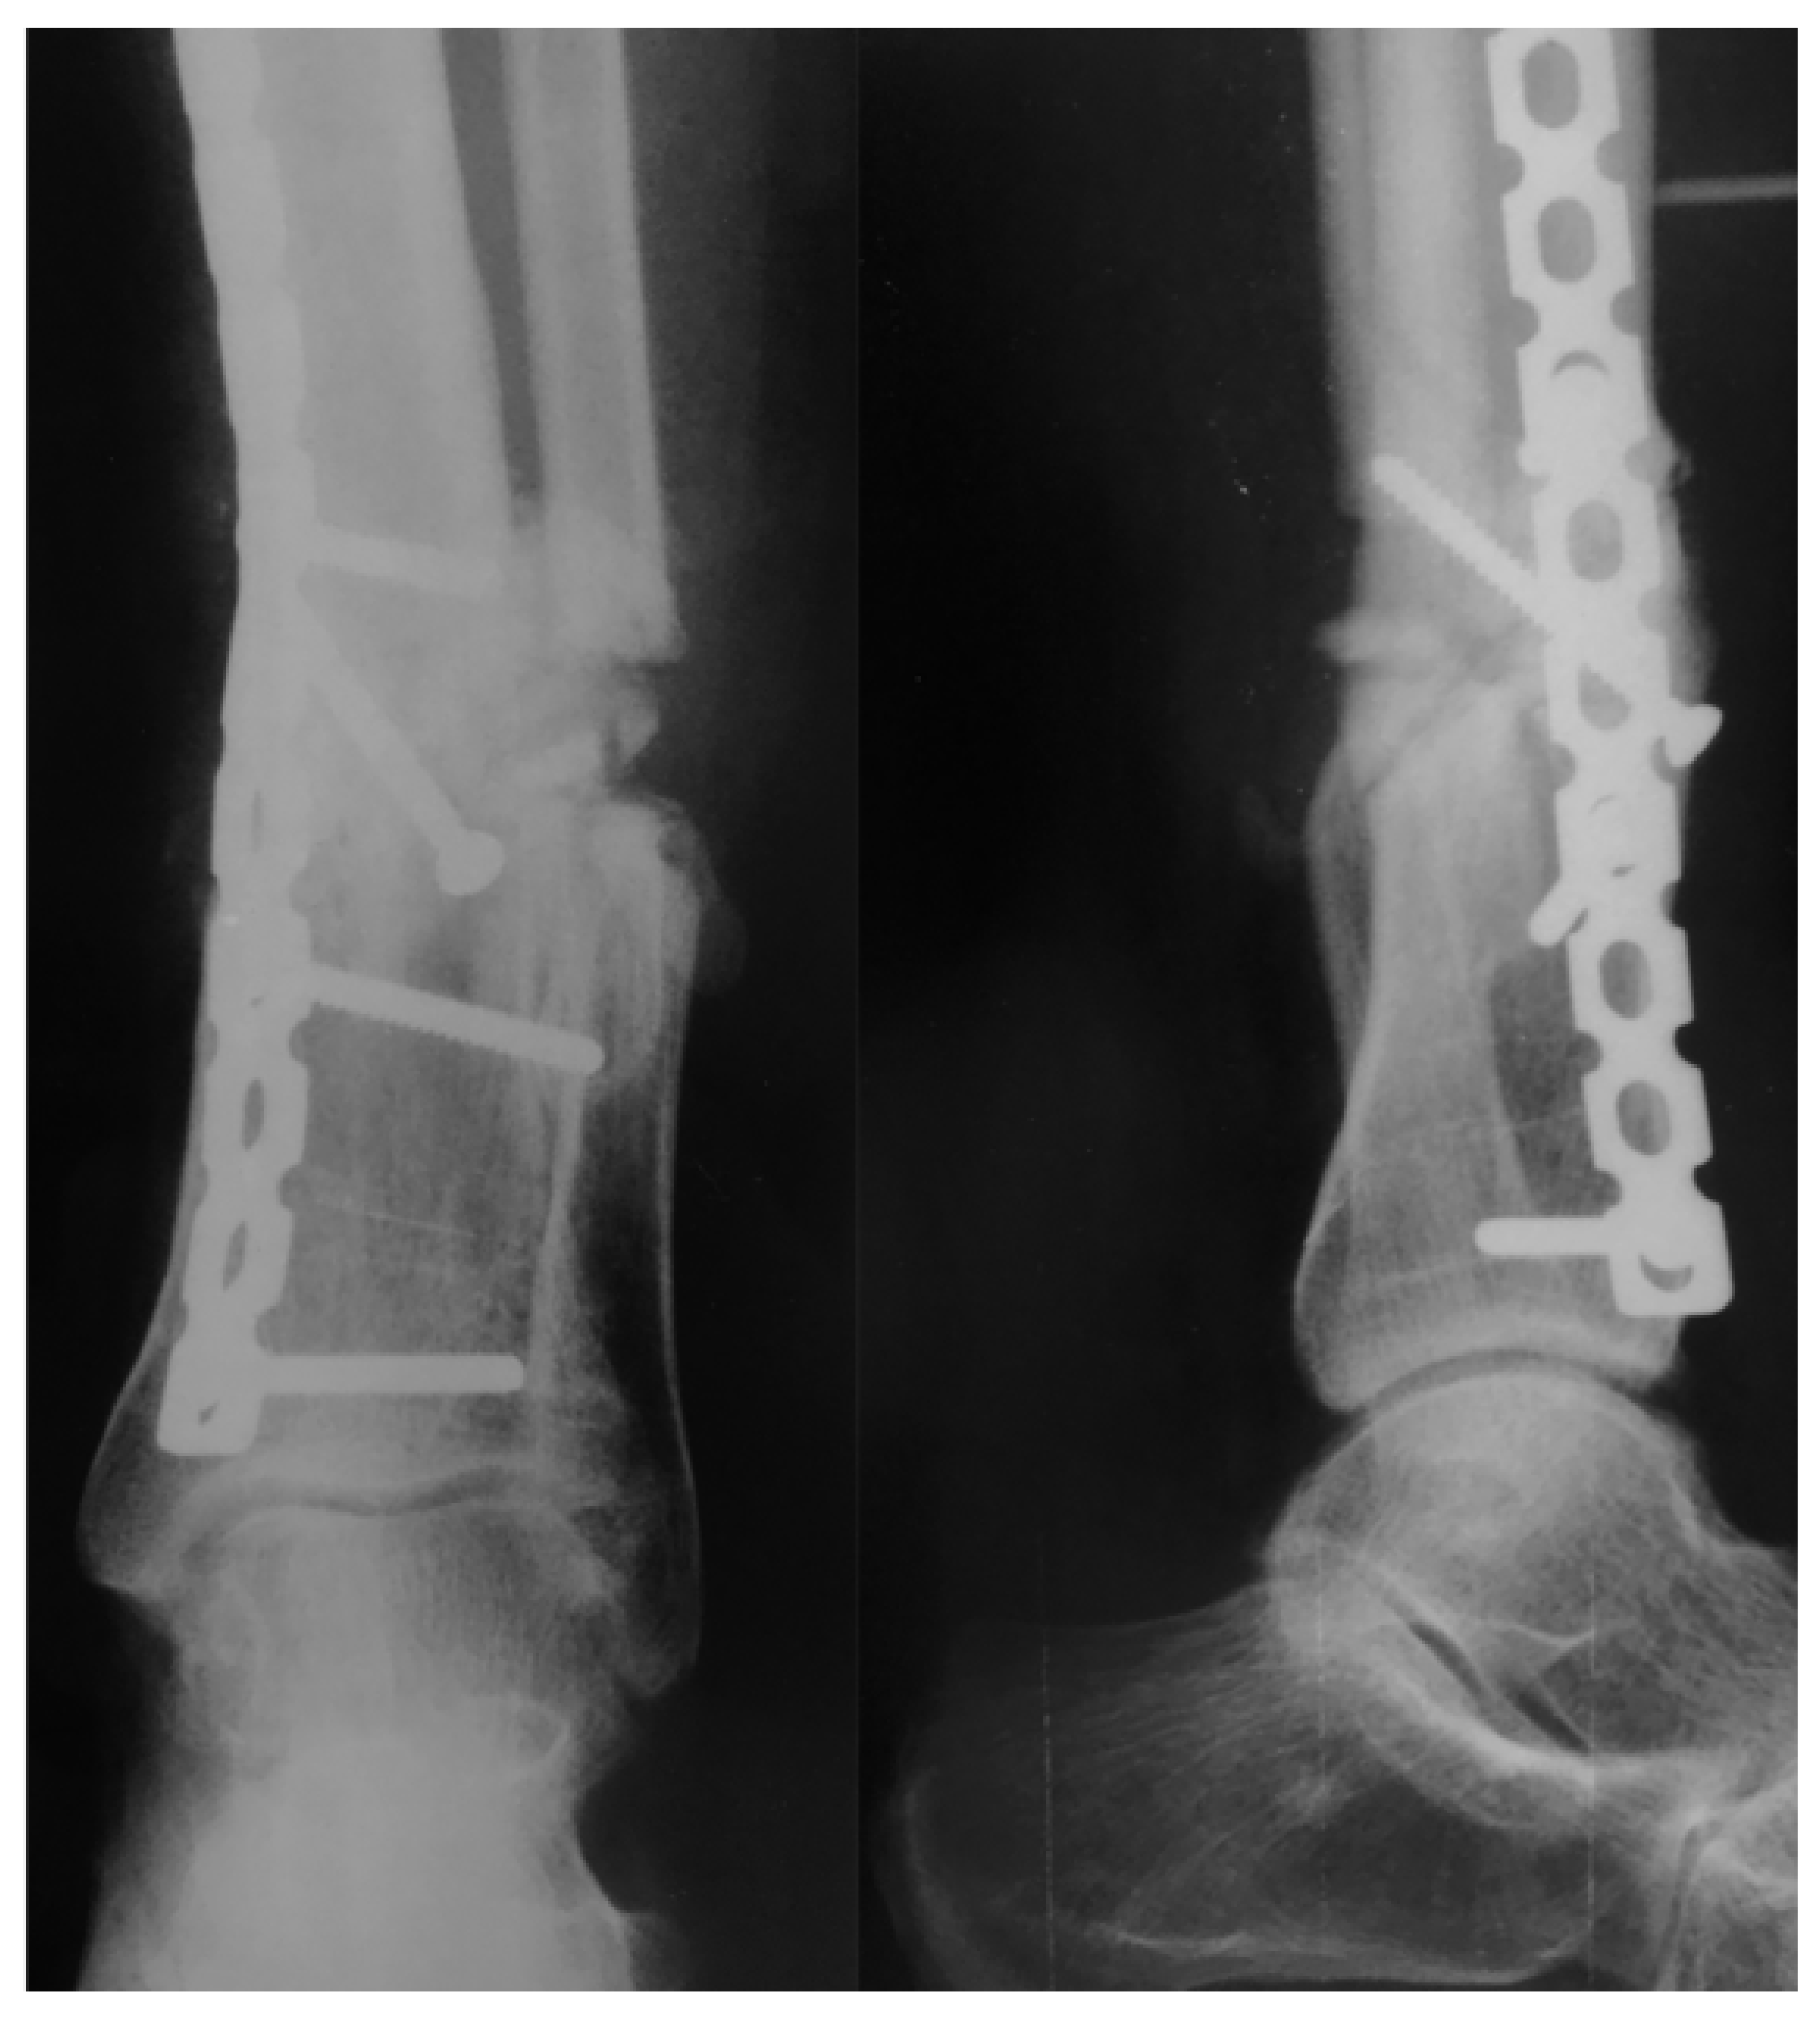

2. Case Report